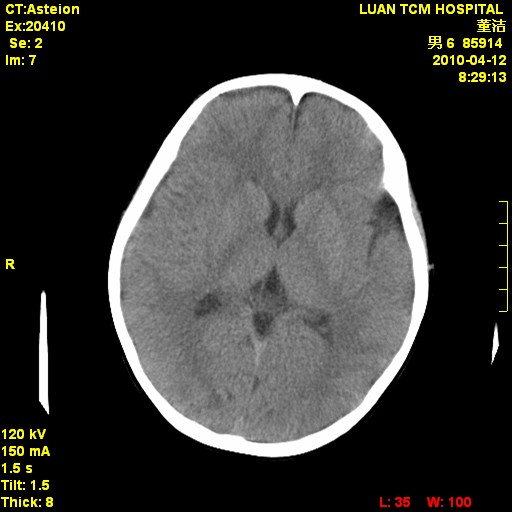

标题: PED3404:有结果,先猜猜这是啥病表现?男,12岁。 [打印本页]

标题: PED3404:有结果,先猜猜这是啥病表现?男,12岁。

考虑右侧额顶部颅内脑外血肿(edh可能)。

无病史无骨窗,无水肿无占位征象,右侧额顶部颅内血肿,或脑膜瘤。建议结合病史。

右侧额顶部自颅板向内近似半圆高密度影,周围无明显水肿,考虑:脑外血肿?脑膜瘤?淋巴瘤?